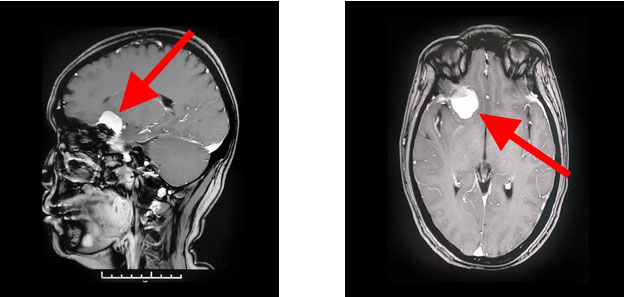

為尋求進一步治療,經(jīng)親友推薦,胡女士慕名前來上海藍十字腦科醫(yī)院。入院后,行頭顱磁共振增強掃描后確認,患者右側(cè)顱底蝶骨嵴-鞍結節(jié)區(qū)實性占位,考慮為腦膜瘤且血供豐富;右側(cè)大腦前動脈A1段與瘤灶貼近。

▲ 蝶骨嵴腦膜瘤周圍多重要神經(jīng)血管

上海藍十字腦科醫(yī)院神經(jīng)外科主任沈建康教授指出,患者的腦腫瘤直徑約3厘米,只有“鴿子蛋”大小,體積并不大。但蝶骨嵴腦膜瘤由于位置比較特殊,腫瘤有可能和血管神經(jīng)粘連緊密,手術難度和風險都很大。如果沒有做到全切除,腫瘤易復發(fā),可能需要再次手術;術中若損傷瘤體周圍神經(jīng)血管,則可能導致患者殘疾,甚至危及生命。

▲ 術后影像顯示,腫瘤已被切除